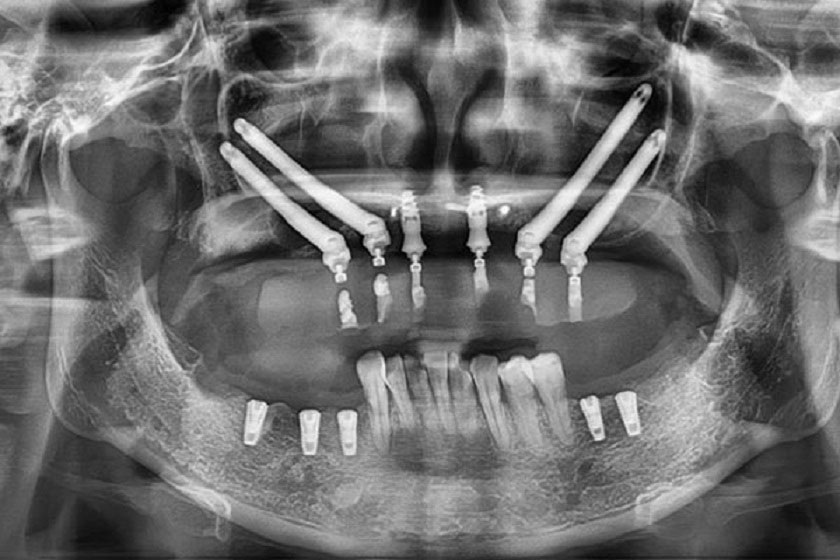

Công nghệ định vị X-Guide có hệ thống camera kép giúp bác sĩ tại phòng khám nha khoa theo dõi hoạt động, đường đi của mũi khoan khi ở trong xương hàm, màn hình hiển thị chính xác tương quan giữa mũi khoan và cấu trúc hàm mặt của khách hàng, giúp việc đặt trụ đạt độ chính xác từ độ sâu, góc nghiêng đến vị trí. So với phương pháp cấy ghép dựa trên kinh nghiệm của bác sĩ thì việc sử dụng công nghệ định vị đã giúp độ chính xác tăng lên gấp 11 lần.

Độ chính xác tăng lên gấp 11 lần với công nghệ định vị X-Guide trồng răng Implant